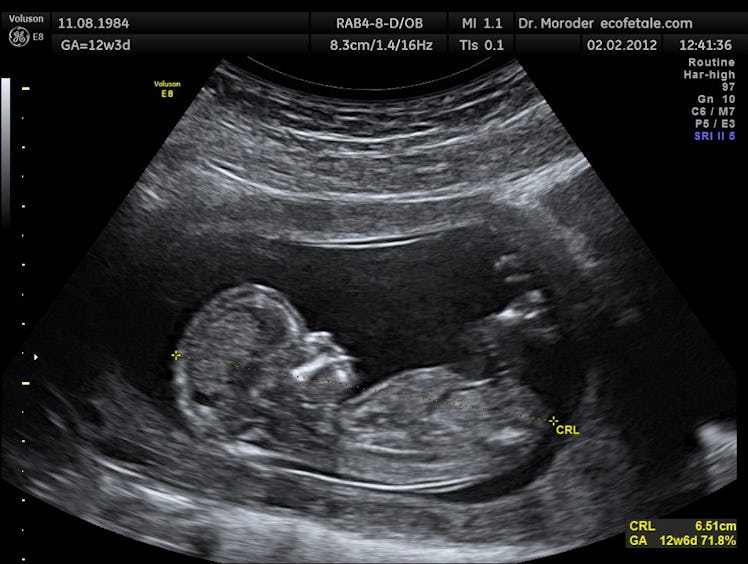

Birth defects impact one out of every 33 babies in the U.S., and are a leading cause of death among infants. But we still have no idea why most of them happen and, according to a new study, scientists are still unable to establish cause in roughly 80 percent of cases. Which means thousands of distraught moms and dads are left looking for answers.

The aim of the study, published today in The BMJ, was to establish the causes of major birth defects in children born between 2005 and 2009, using Utah’s population-based surveillance system. Out of 270,878 births, Feldkamp and her team identified 5,504 children with birth defects. They were able to assign definite causes—almost all of them genetic, but a handful based on environmental factors—to 1,114 cases, or about 20 percent. But when it came to the remaining 79.8 percent of babies born with defects, the researchers were stumped. It’s important to note that Utah’s birth defect surveillance system excluded some more common birth defects, like clubfoot, which may have resulted in a lower prevalence rate overall. But this alone cannot explain the absence of cause in nearly 80 percent of cases.